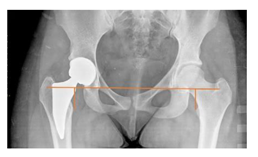

Plain radiographs were evaluated preoperatively and at the most recent follow-up, after appropriate calibration. Positional parameters were assessed according to values guidelines from published literature, as listed in Table 1 [23,24,25,26,27,28,29,30,31]. Femoral stem and acetabular cup osteointegration were quantified according to Engh [32] and Moore scale [33]. Heterotopic ossifications were graded according to the Brooker system [34].

3.4. Radiographic Evaluation

Preoperative and postoperative radiographic data are reported in Table 4. Preoperatively, 18 THR (24.3%) were implanted in skeletally immature children with closed triradiate cartilage (1 ≤ Risser ≤ 3). Radiographic acetabular insufficiency (LCEA < 25° and AI > 13°) was detected in 14 hips (18.9%), while protrusion was present in 3 hips (4.1%) An excessive valgus of the femoral neck was observed in 19 hips (25.7%), while an important varus deformity was present in 7 hips (9.5%).

Preoperative and postoperative radiographic parameters. All results are expressed as crude numbers for dichotomous variables and as mean ± Standard Deviation for continue variables. LCEA: Lateral center-edge angle. * Varus inclination is expressed as negative value, positive value for valgus.

Postoperative radiographs showed a significant vertical malposition of the cup in 1 case (1.4%), a significant varus stem in 8 cases (10.8%) and a significant valgus stem in 1 case (1.4%). Two patients (2.7%) showed moderate heterotopic bone formation (Brooker ≥ 2), that did not significantly affect the hip motion and symptoms. All those THR that did not undergo revision showed good radiographic osteointegration, with no evidence of implant breakage, radiographic lucencies, bone defects, cup migration, or stem subsidence at the most recent radiographs.